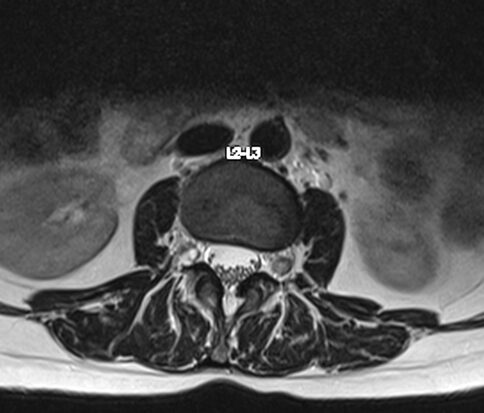

Resonancia Magnética de columna lumbar

“QUISTES PERINEURALES”

Los quistes perineurales son quistes llenos de líquido cefalorraquídeo en las raíces nerviosas, localizados principalmente en la zona sacra de la columna vertebral, aunque pueden encontrarse en cualquier sección de la columna vertebral; pueden causar una radiculopatía progresivamente dolorosa. Las mujeres se ven afectadas con mayor frecuencia que los hombres. Los pacientes con quistes perineurales presentan dolor en la zona de los nervios afectados por el quiste, debilidad muscular, dificultad para sentarse durante periodos prolongados, pérdida de la sensibilidad, pérdida de reflejos, dolor al estornudar o toser, inflamación en la zona sacra, parestesias, dolor de cabeza, ciática, y disfunción intestinal, de vejiga y sexual.

El diagnóstico se basa en la resonancia magnética.